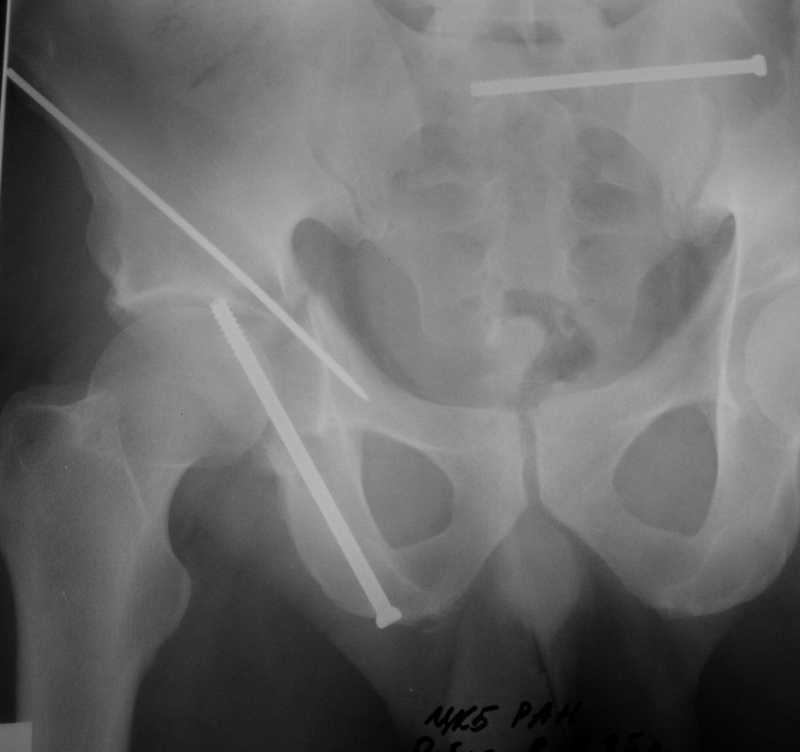

Yordan! In this case position of bone fragments is quite good. We

prefer to use miniinvasive technique. We fix posterior column by can. screw and put 3mm pin with distal thread to the anterior column. Next day after the surgery he may start walking with crutches. 3 month after the surgery we remove the pin. In cases of maleolar fractures we use

Sending exampl pict.